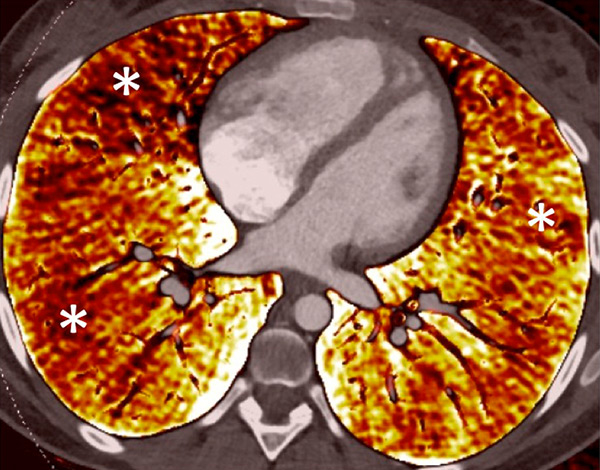

Figure 6

Perfusion heterogeneities in idiopathic pulmonary artery hypertension (stars) in two different patients (A/B). The dilatation of the arteries in pulmonary hypertension (arrows) is not always observed depending on the severity of pulmonary hypertension.